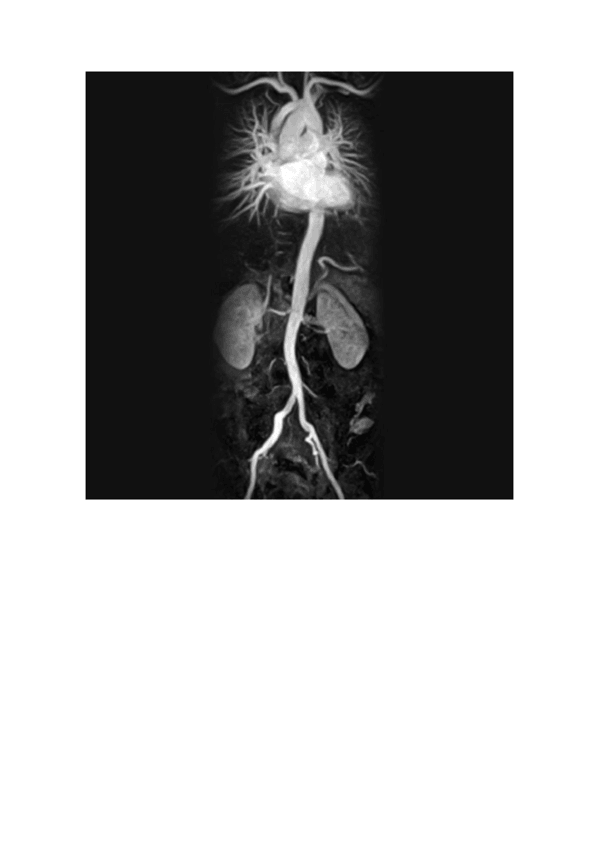

5 - Aparatos circulatorio y respiratorio

He publicado nuevos apuntes de Anatomía por la imagen: 5 - Aparatos circulatorio y respiratorio

Angiografia.pdf